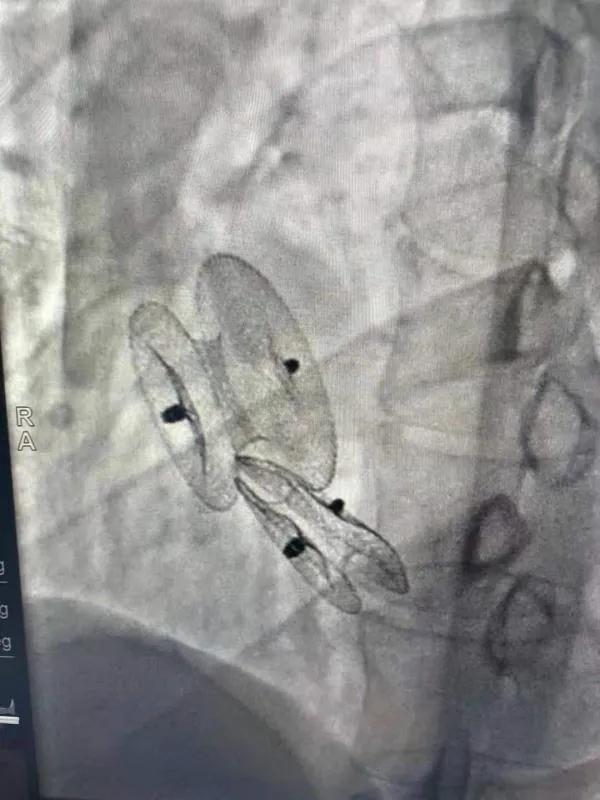

先天性心臟病房間隔缺損呈多孔型怎么辦?患者并非只能選擇開胸手術(shù)。近日,西安國際醫(yī)學(xué)中心醫(yī)院心臟病醫(yī)院成功開展一例雙孔房間隔缺損雙傘介入封堵術(shù)。

房間隔缺損是先天性心臟病的一種,介入手術(shù)相較于傳統(tǒng)的外科手術(shù)損傷小,風(fēng)險(xiǎn)相對較低,術(shù)后恢復(fù)快。一般的房間隔缺損多呈單孔,封堵難度較小,而雙孔房間隔的封堵難度大大增加,至今僅有國內(nèi)頂尖的封堵專家成功完成了數(shù)例而已。

患者是位27歲的年輕女性,經(jīng)常感到心慌,心臟超聲發(fā)現(xiàn)房間隔缺損,并且房間隔缺損呈雙孔型,大的約14mm,小的約9mm,兩個(gè)缺損間相隔較遠(yuǎn),介入封堵難度非常大。

在詳細(xì)了解患者病情,仔細(xì)閱讀患者影像資料后,曾廣偉主任已經(jīng)有了清晰的手術(shù)策略。在精心的準(zhǔn)備和團(tuán)隊(duì)的配合下,曾主任順利的利用兩個(gè)封堵器對房缺進(jìn)行了封堵。